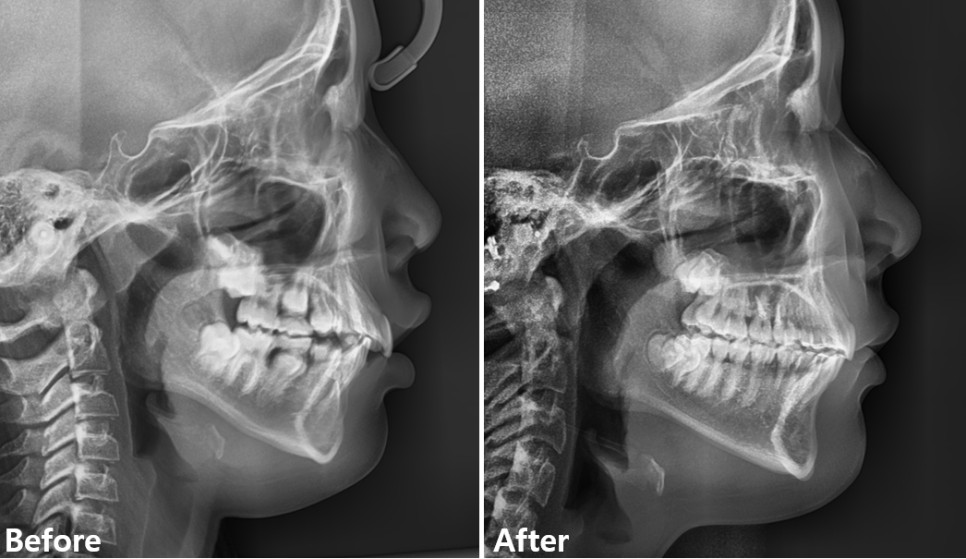

???? 골격성 2급 부정교합 교정 병행

이 환아는 **골격성 2급 부정교합(상악이 상대적으로 전방위치)**을 동반하고 있었기 때문에,

상악 구치부에 미니스크류를 식립하고 상악 치열 전체를 후방 이동시켰습니다.

보통 어린이 2급 부정교합에서는 헤드기어를 많이 사용하는데, 이 환아는 헤드기어 착용을 거부하여

미니스크류로 치아를 후방이동시켜서 교합을 맞추기로 하였습니다.

상악 치아의 후방이동으로 인해 측모(옆모습)에서 돌출감이 완화되고,

상하악 전치간의 넓었던 수평피개가 정상적으로 개선되었습니다.

7f829c6152fc0f266ad641c0f7ec26e1_1763090029_6644.png

판교교정치과 / 치료 전 후 측면 엑스레이 비교

다만, 교정 막바지에 사춘기에 접어든 아이가 “이제 빨리 교정 끝내고 싶어요!”라며 졸라서,

정중선을 다 맞추지 못한 상태에서 마무리하게 되었습니다.

하지만 매복된 측절치는 치근까지 잘 배열되었고, 잇몸 형태도 주변치아와 비슷하게 자연스럽게 회복되었습니다.